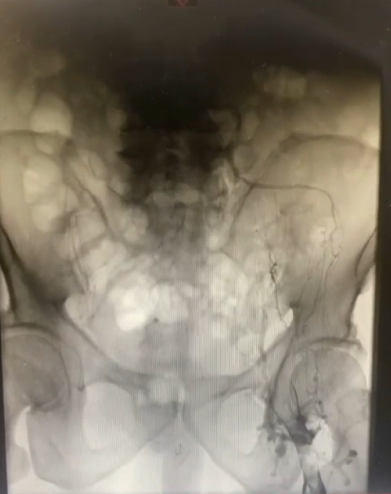

手术过程(二):8F鞘穿刺左侧腘静脉,造影见股浅静脉内充盈缺损,血液回流速度慢,髂外静脉内大量充盈缺损,髂总静脉未见显影,周围侧支循环开放。

手术过程(三):导丝通过髂总静脉略有阻力,交换stiff导丝后,引入DVT血栓抽吸导管,连接AngioJet血栓抽吸装置,于髂股静脉处喷射配置好的20万IU尿激酶,20分钟后,再次引入导管,改为抽吸模式,在髂股静脉血栓内抽吸,部分团块较大的血栓往返抽吸数次。

手术过程(四):退出抽吸导管后,复查造影,股浅静脉内血栓消失,但血流速度仍缓慢,提示近心端仍有梗阻。使用高压球囊扩张髂静脉,可见髂总静脉明显狭窄。分段扩张完成后,引入12 mm×40 mm球囊继续扩张。